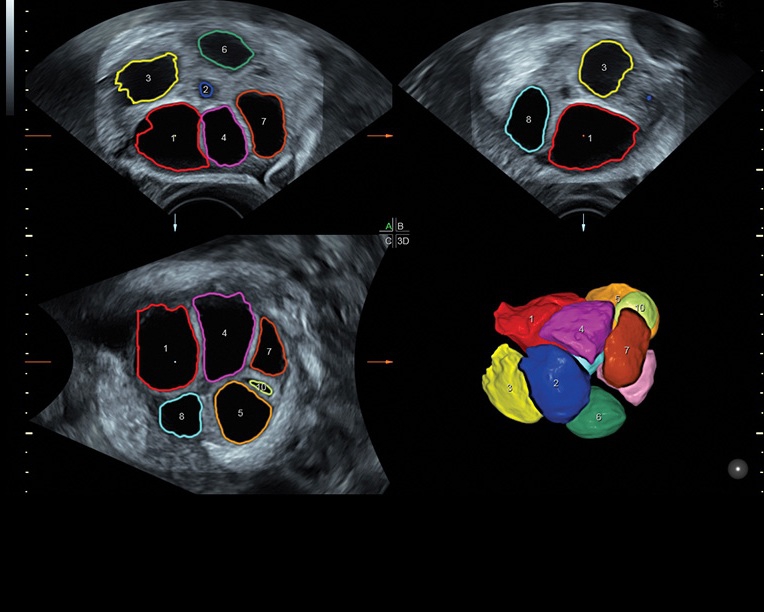

Система предназначена как для коммерческой, так и для государственной медицины, в клиниках с высокой загруженностью пациентами. Voluson S8 отлично справляется с большим объемом работы благодаря шаблонизированным отчетам и автоматизации обработки и постановки диагнозов с помощью функций SonoNT, SonoVCAD, SonoAVC и STIC. Это делает аппарат коммерчески выгодным и окупаемым в ближайшей перспективе.

• Сложные инструменты для оценки качества плода: Сканер оснащен инновационными инструментами, позволяющими проводить детальную оценку состояния плода, включая его сердечную деятельность, анатомию и кровоток.

Технологии, доступные на ультразвуковом сканере Voluson S8:

• Технология SonoRenderlive: Эта технология облегчает получение 3D/4D изображений путем автоматического изменения положения плоскости визуализации в зависимости от движений плода. Она позволяет получить реалистичные и объемные изображения, что полезно для демонстрации плода будущим родителям и для дополнительного анализа.

• Программа для исследований сердца плода с возможностью цветовых допплеровских и ангиографических исследований на основе анализа пространственно-временной корреляции изображений (STIС)

• Программное обеспечение для исследования сердца плода в режиме 3D/4D (быстрый доступ к плоскостям сканирования) по рекомендациям ISUOG